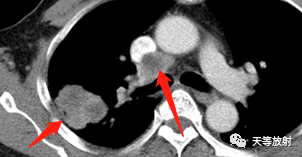

实性结节呈分叶状改变,邻近胸膜增厚,有牵拉改变,凹陷征。